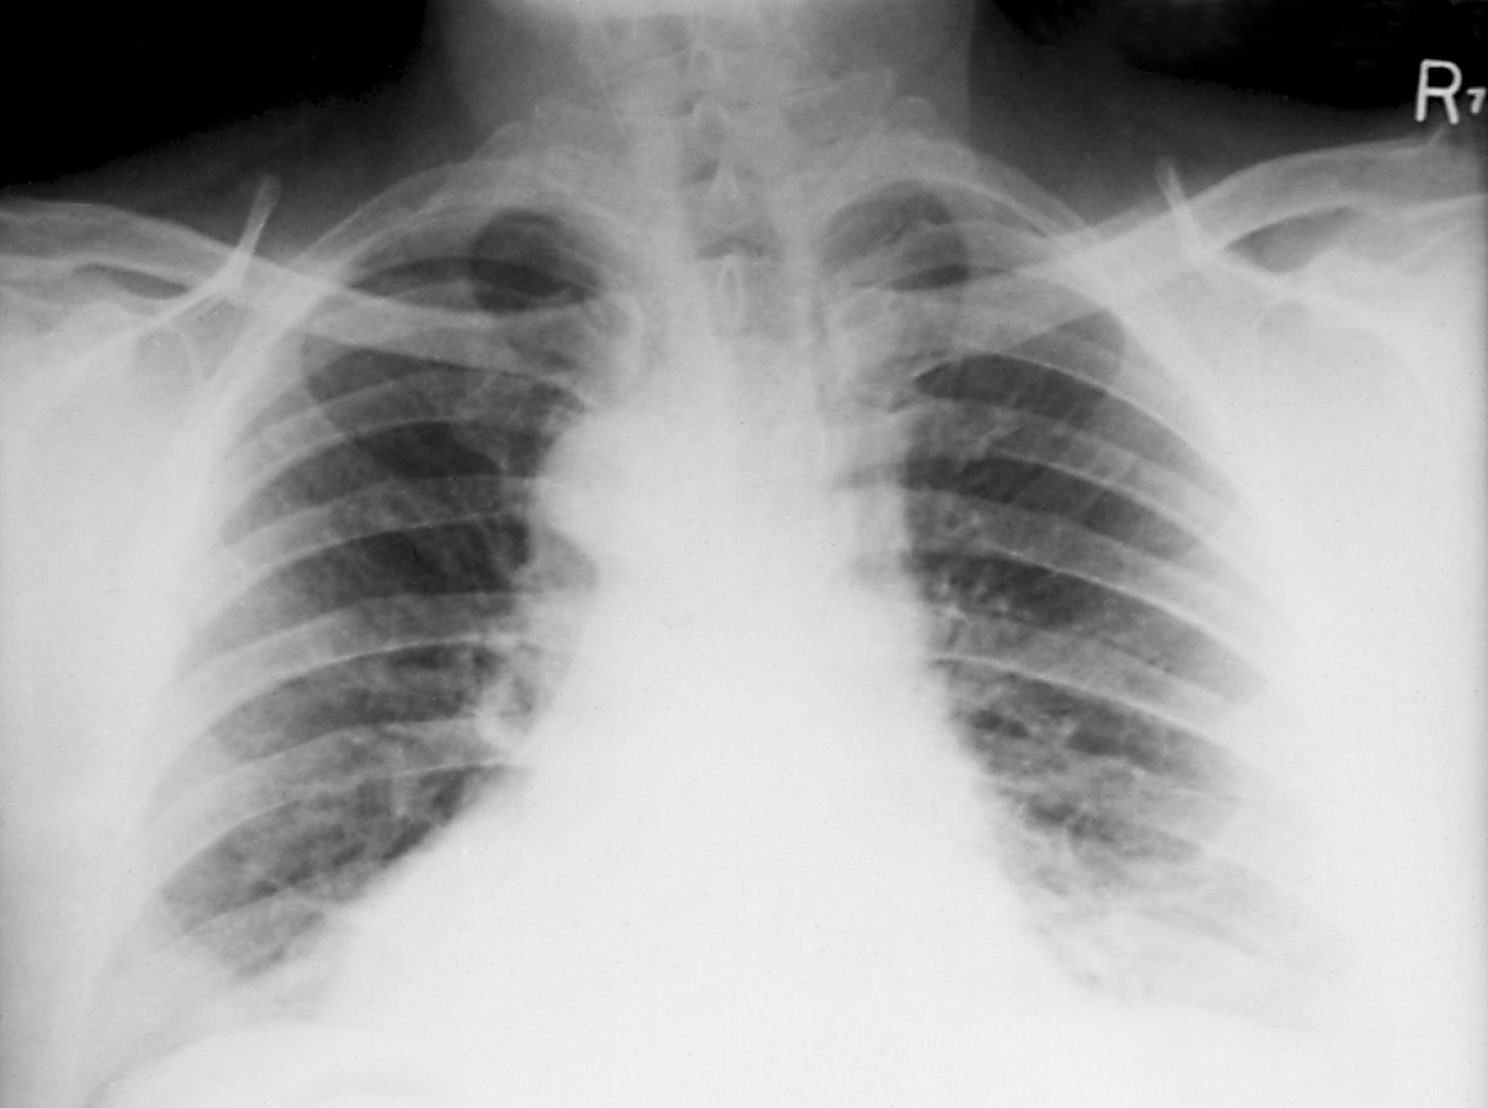

Inhalation anthrax can occur when a person breathes in anthrax spores. It's the deadliest form of the disease. People who work in places such as wool mills, slaughterhouses, and tanneries may breathe in the spores when working with infected animals or contaminated animal products. Inhalation anthrax starts primarily in the lymph nodes in the chest before spreading throughout the rest of the body.